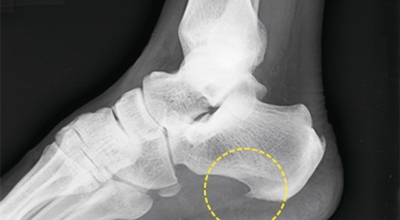

족저 근막염은 염증에 의한 훼손 및 통증을 유발하는 질환인데요 족저 근막염 증상은 동일한 발뒤꿈치 통증 하글런드 병변의 기형으로 알려져 있으고 아킬레스 건과 연관이 깊다고 해요. 특히 근육이 덜 풀린 아침 시간 대는 보행 시 날카롭고 바늘로 찌르는 듯한 심한 통증을 느끼게 된다고 해요. 하지만 아침 시간 대를 지나 오후에 접어들면서 일정 양 통증은 서서히 감소하기 시작한다고 하는데요 초기 증상이 나타난다면 필수로 전문의를 찾아 조기치료하는 것이 바람직해요.

비수술적 치료로 대부분 족저 근막염 증상이 완화될 수도 있지만 일부 환자는 수술이 필요한 경우가 있어요. 수개월간의 비수술적 치료를 했음에도 발 통증이 계속되면 수술을 고려해봐야 하며 수술을 통해 족저 근막을 증가시키는 방법을 고려해 볼 수 있다고 해요.

최근 관절경을 이용해 족저 근막 절개술을 시도하기도 하는데 수술적 치료의 성공률은 70~90%로 높게 알려져 있어요. 하지만 수술 후 신경 훼손 등과 같은 합병증이 유발될 수 있기 때문에 잘 알아보고 전문의와 상담후 수술을 결정하시는게 좋답니다.